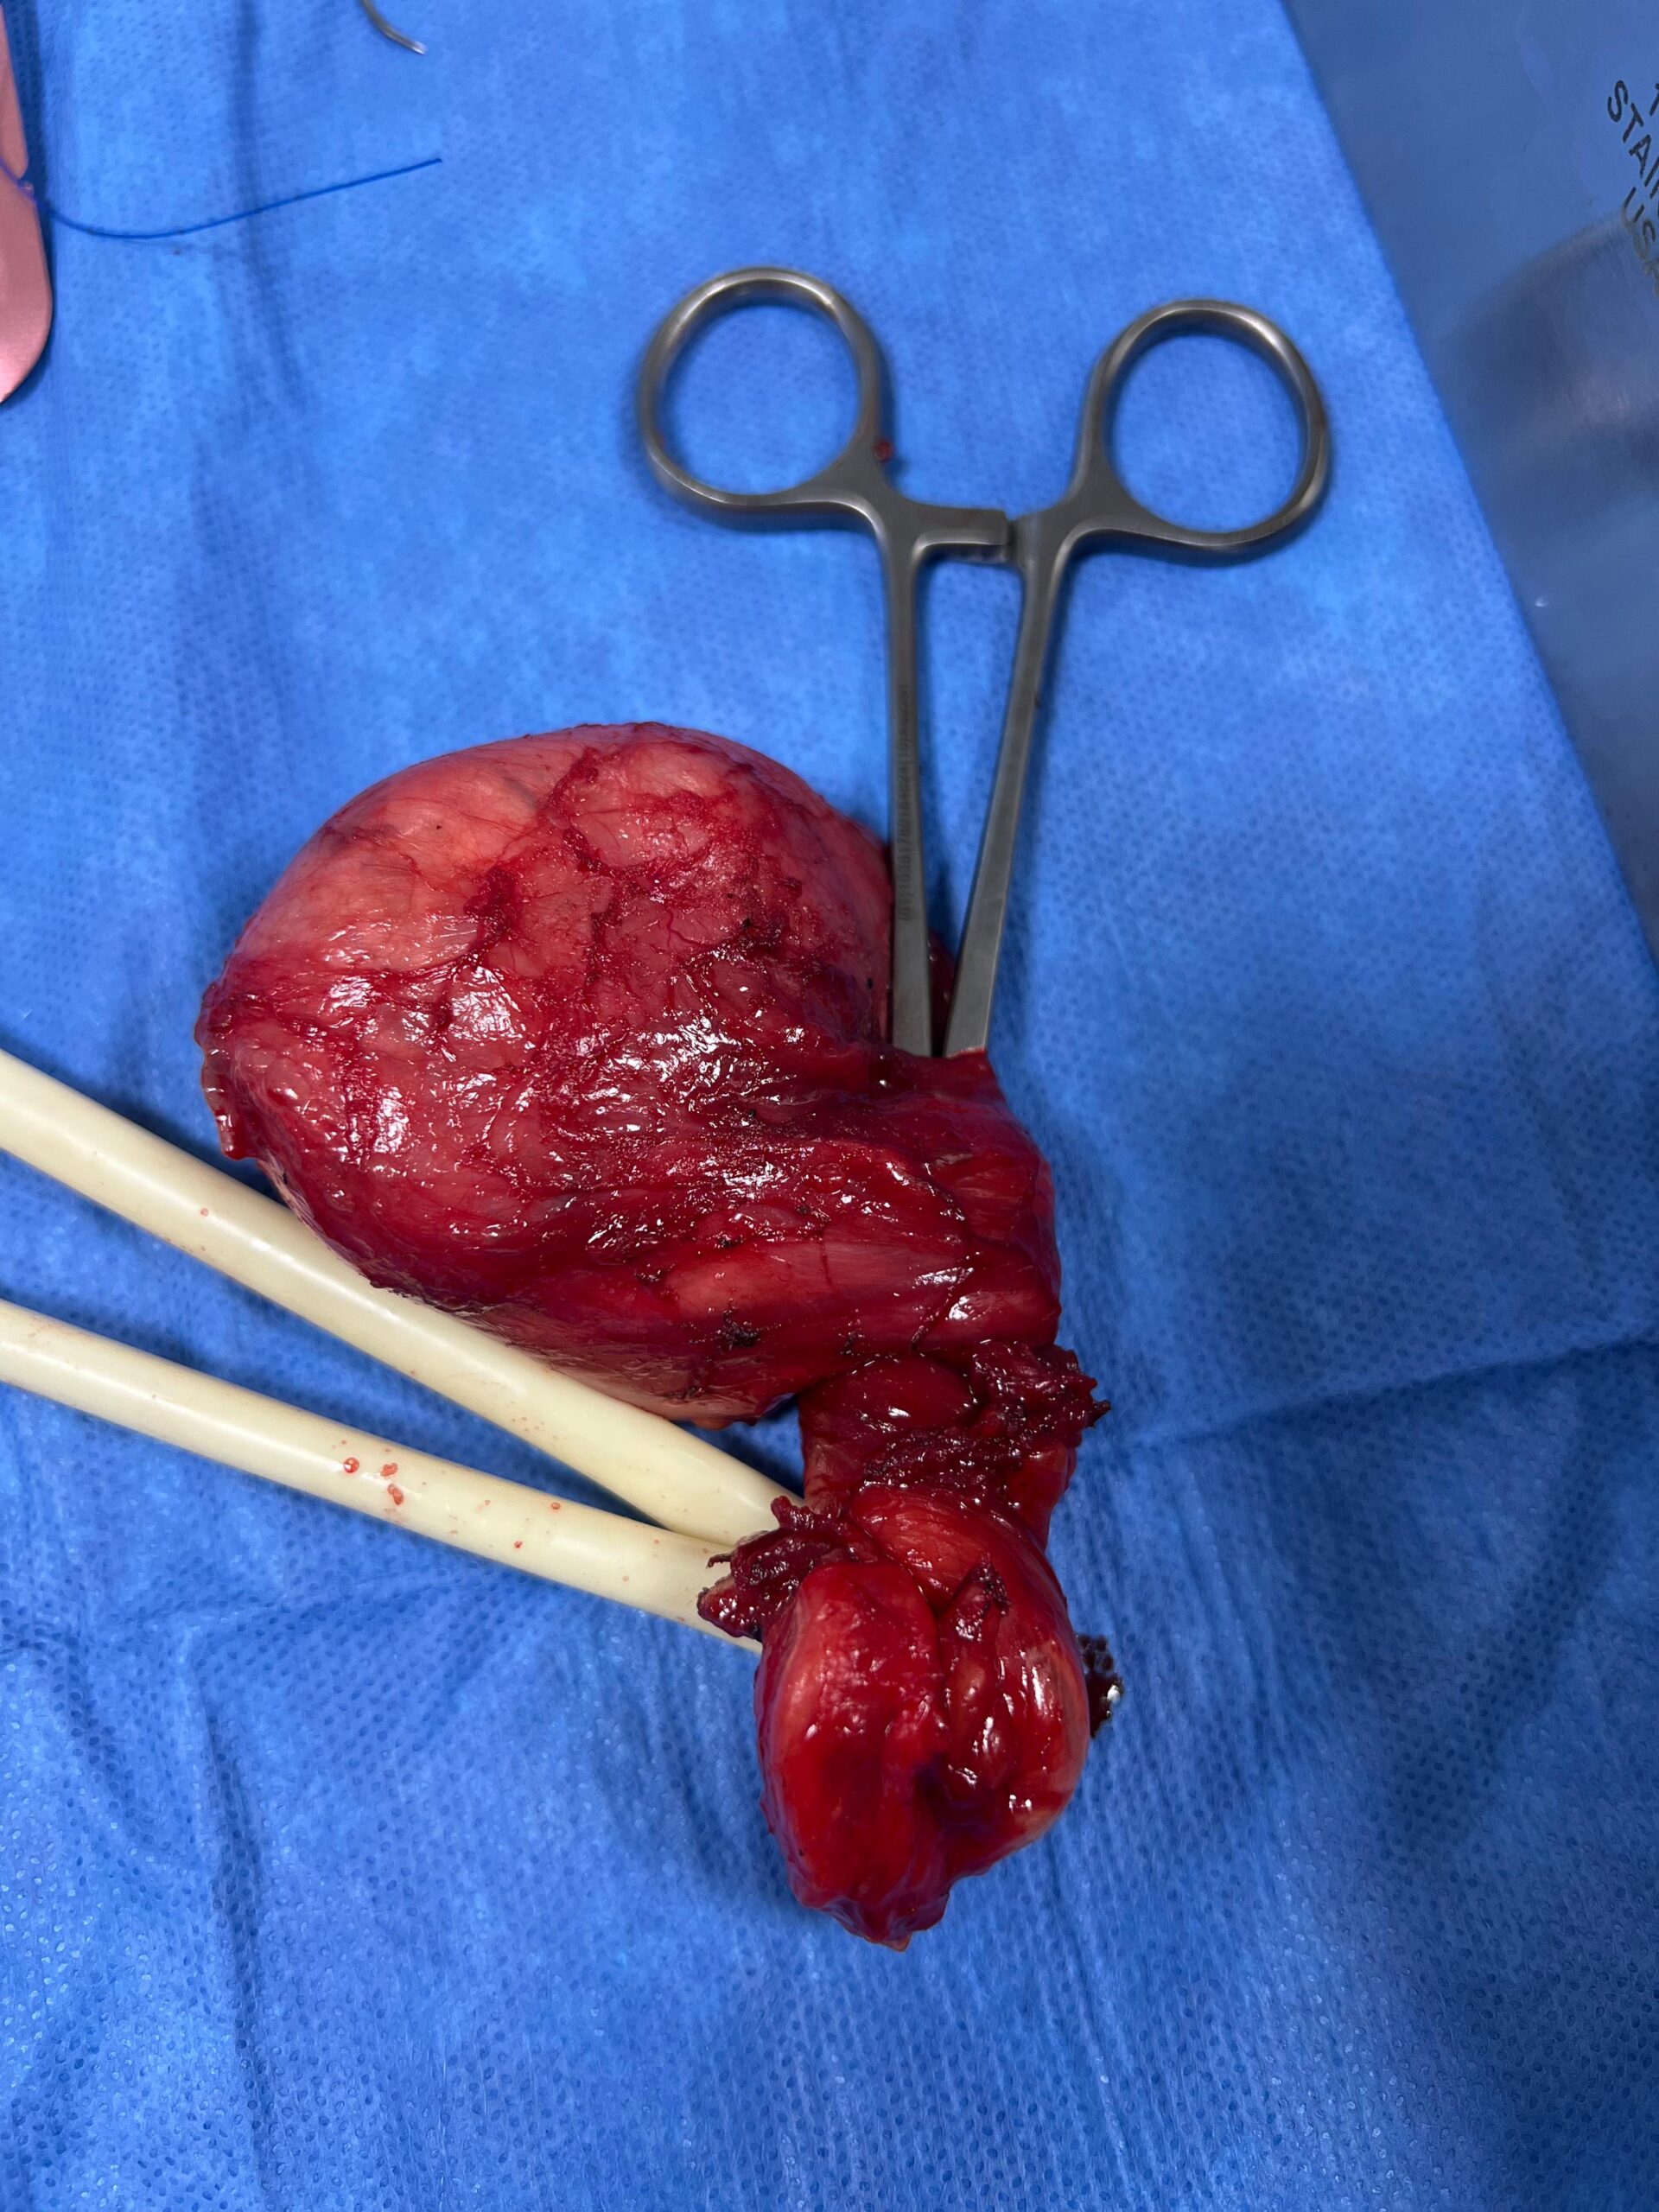

Disfunción Eréctil con Enfermedad de Peyronie’s (curvatura severa del pene).

- La enfermedad de Peyronie’s ocurre cuando se forma una placa de tejido cicatricial en el pene, causando curvatura, dolor y dificultad durante la erección.

- En este paciente, realizamos una incisión de placa para liberar la curvatura, colocamos material protésico de refuerzo (graft) para estabilizar el tejido y finalmente implantamos una prótesis peniana inflable multicomponente.

Beneficios del procedimiento:

- Corrección de la curvatura

- Restauración de la función eréctil

- Mejora en la calidad de vida sexual

- Procedimiento seguro, mínimamente invasivo y con alta satisfacción de pareja.